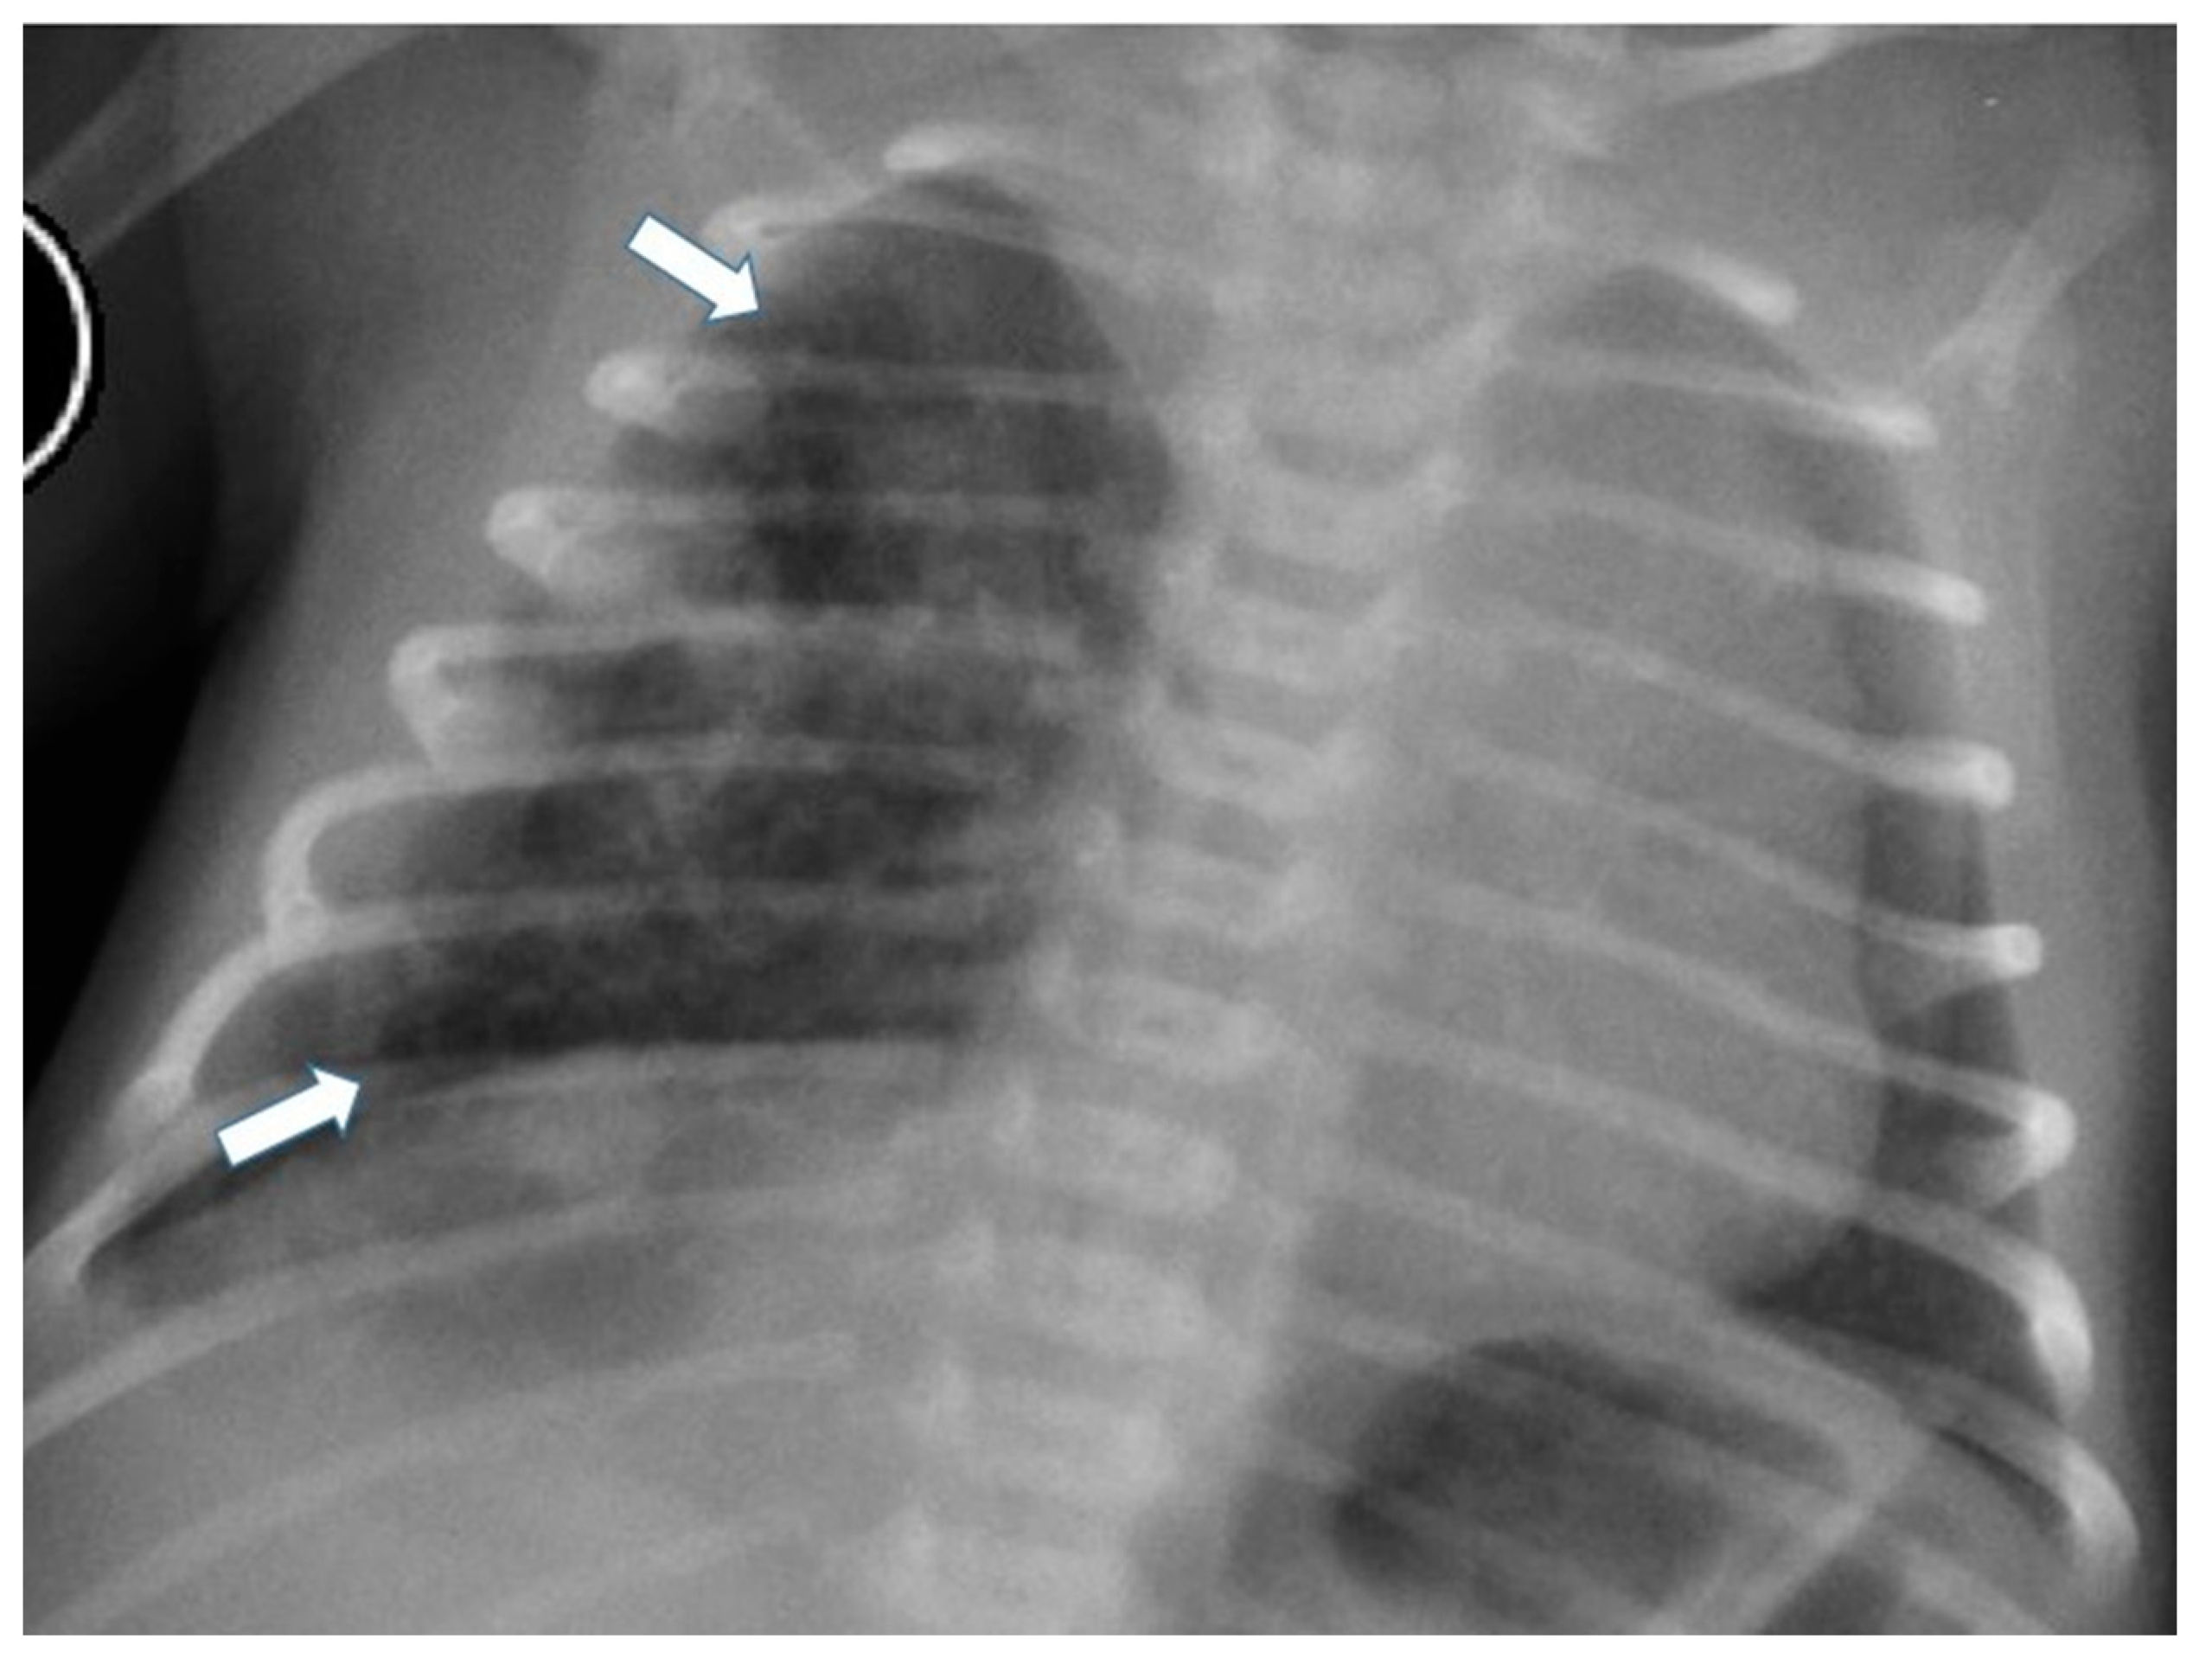

Figure 4.

Chest radiograph of a newborn shows multiple small air-filled cysts in the right upper lobe and right lower lobe (arrows), suggesting a type 2 CPAM.

CT allows for the better evaluation of the lesion and its relationships with adjacent structures. On CT scans, lesions are detectable as well-defined air-filled spaces variable in size depending on CPAM type [15]: type 1 CPAM appears on CT as a one or multiple large cystic structures which can be entirely filled with air or with air-fluid levels (Figure 3, Figure 5 and Figure 6); type 2 CPAMs are visualized on CT as air-filled multicystic masses or focal or ill-defined areas of consolidation [3,15] (Figure 4 and Figure 7); type 3 typically exhibits a solid appearance on CT [15]. In infected CPAMs, imaging can demonstrate internal air-fluid levels and an enhanced thick wall.